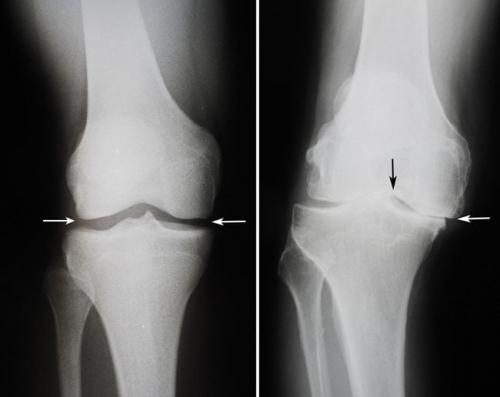

- Комплексные суставы (articulatio complex) — имеют суставной диск или мениски (грудино-ключичный, височно-нижнечелюстной, коленный).

Комплексный является двухкамерным, поскольку имеет внутрисуставный хрящ, который разделяет его на две камеры. Таким является коленный.

В некоторых случаях по краю сустава концы костей неплотно прилегают друг к другу, образуя зазоры. Эти зазоры восполняются дополнительными хрящевыми вкладышами — менисками. Они выполняют стабилизирующую сустав и амортизирующую функцию. Самые большие мениски находятся в коленных суставах. Тем не менее есть и другие суставы, содержащие мениски, такие как височно-нижнечелюстной, грудино-ключичный или акромиально-ключичный.

Сложные суставы - соединения костей скелета, при которых присутствуют внутрисуставные включения в виде дисков (височно-нижнечелюстной сустав), менисков (коленный сустав) или мелких костей (запястный и заплюсневый суставы).